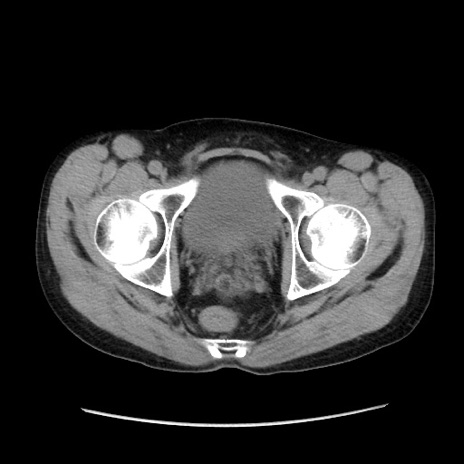

症例37(横断像)

冠状断像

【症例】40歳代 男性

【主訴】腹痛

【現病歴】4時間ほど前に電車に乗車中に臍部上より腹痛出現。徐々に増悪し起立困難となり、救急外来受診。生ものは数日食べていない。今朝お雑煮を食べた。

【身体所見】BT 36.8℃、BP 117/84mmHg、HR 91/min、SpO2 97%、苦悶様、腹部:臍上部広範囲圧痛あり、反跳痛±

【データ】WBC 8100、CRP 0.03